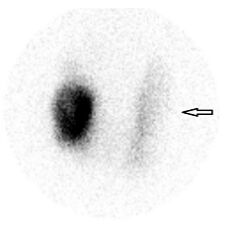

33.下圖為99mTc-MDP骨骼掃描影像,箭頭所指之不正常攝取最不可能為下列何者?(A)中風 (B)原發性腦瘤 (C)代謝性骨病變 (D)腦轉移病灶